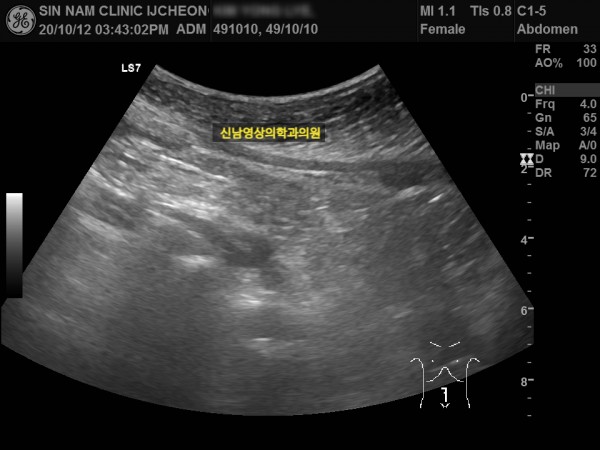

본 환자분께서는 사흘 정도 지속되는 복통과 고열로 내원하신 60대 중반의 환자분입니다.

복통 부위의 병변을 확인하기 위해서 복부 촬영과 복부 초음파검사를 진행했고, 맹장은 이상이 없고, 대장 주위로 복강삼출액(물)이 둘러싸고 있으면서 상행대장부위의 부종이 심하게 발견되었습니다.

원내 피검사상 백혈구 수치가 높아 대학병원 응급실로 전원 조치하고 응급수술을 받으셨고...